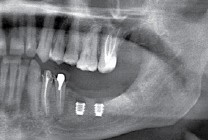

Так вот, чрезмерная атрофия альвеолярного гребня может лишить нас возможности имплантации — нам просто не хватит объемов костной ткани для нормальной установки имплантов. Однако, эта проблема решаема — существует целый ряд методик остеопластики (включая синуслифтинг), позволяющих восстановить любой объем костной ткани в в любом участке зубного ряда с высокой степенью эффективности. И, как правило, хорошие врачи в хороших клиниках так и поступают:

Их можно установить в минимально возможный объем костной ткани, где установка обычных взрослых имплантов невозможна без предварительной остеопластики. В некоторых случаях они даже позволяют избежать синуслифтинга, что, согласитесь, звучит очень заманчиво.